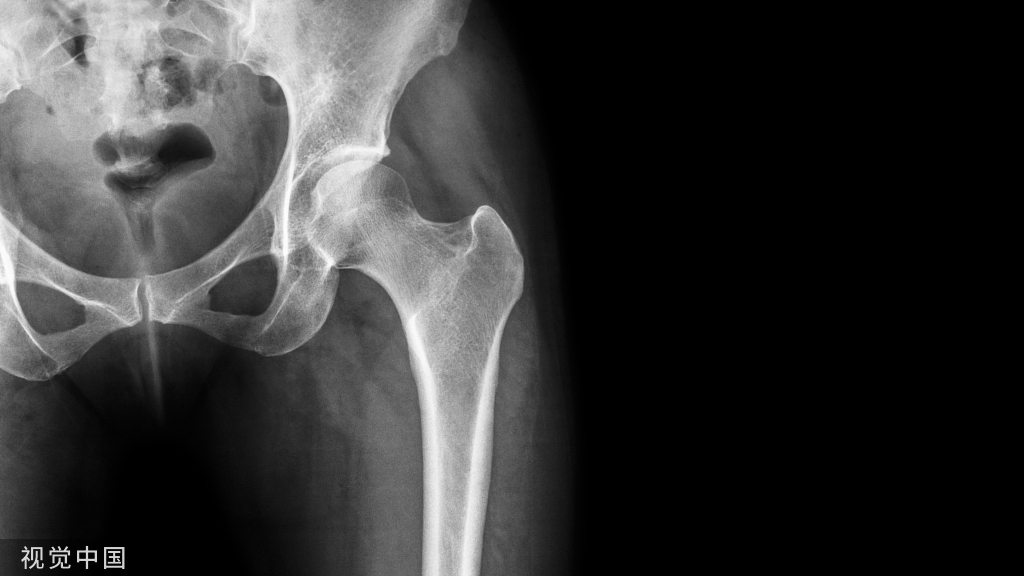

① 四踝骨折示意图:1.内踝;2.外踝;3.后踝;4.胫骨前结节(前踝)。

② 四踝骨折典型病例图。